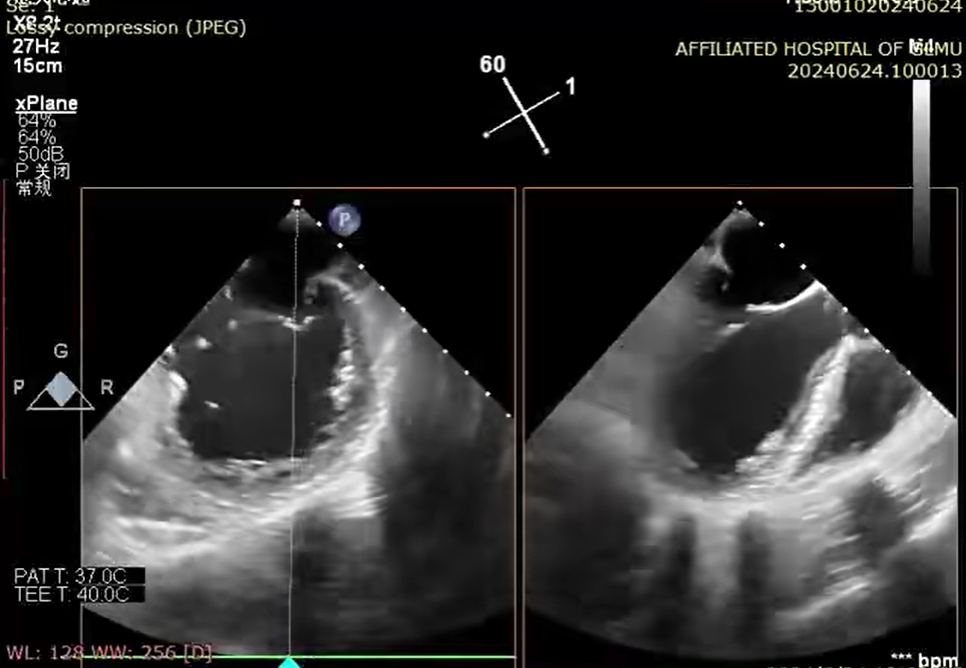

6 月 24 日,心血管内科一病区廖发荣、何武金团队在中山大学附属第一医院庄晓东教授的指导下,在患者右侧腹股沟区穿刺一个 3-5 毫米的小创口,然后将器械通过股静脉穿刺房间隔,把「二尖瓣夹系统」送入患者左心房,进而到达心脏的二尖瓣口,然后全程在食道三维超声引导下,精准夹合二尖瓣后瓣病变区域。

钳夹后,二尖瓣反流从术前 4+改善至 1+、夹合稳定、平均跨瓣压差 2 mmHg,患者术后心功能得到明显改善,无相关并发症,于 6 月 29 日顺利出院。7 月 12 日,患者到医院复查各项生理指标基本正常。